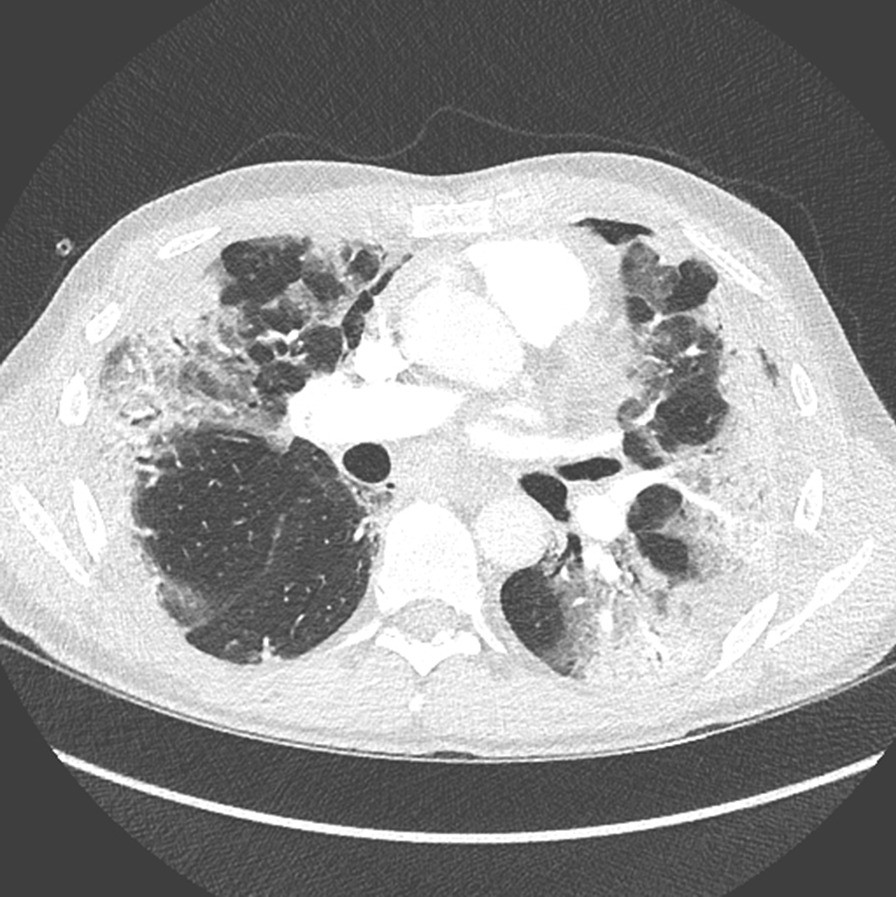

Fig. 2

CT scan after 2 weeks of hospitalisation. In comparison with the initial CT scan, ground glass opacities have been replaced by much more extensive consolidation lesions, especially predominant at the bases. Majoration of bilateral consolidations present in the middle and inferior lobes